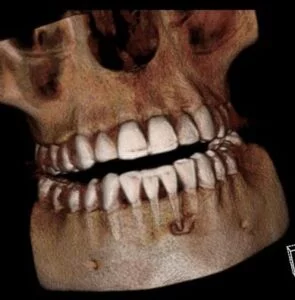

A CBCT was taken after a negative cold test indicated a necrotic tooth. When the CBCT was taken, we could clearly see that the abscess had completely perforated the labial bone at the apex of #24 and was close to doing so on #25.

As we investigated more deeply, we identified another critical piece of information that would affect our treatment plan: a second canal on #24.